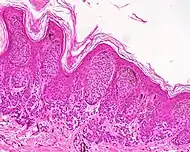

| Junctional nevus | Along the junction of the epidermis and the underlying dermis.[15] | May be colored and slightly raised.[16] | ![]() |

ICD10: D22 ICDO: M8740/0 |